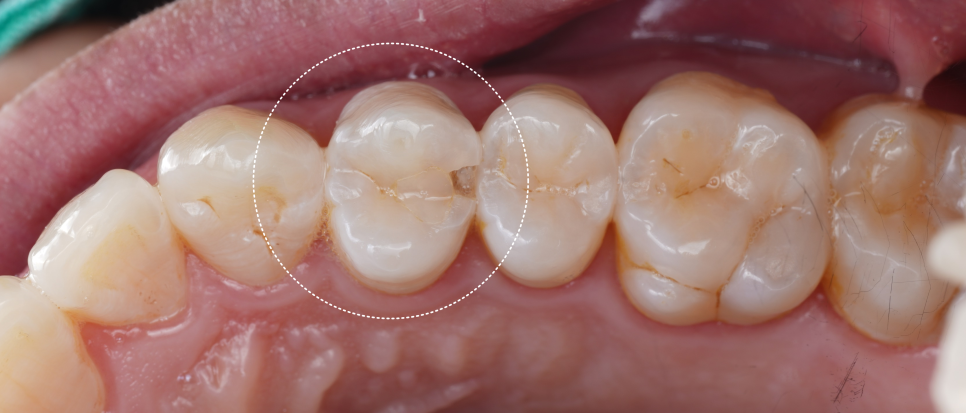

내원 당시 치아는 겉보기엔 멀쩡했지만 기존 레진이 떨어져 그 아래로 세균이 침투한 흔적이 있었어요.

촬영일 : 251020

이를 2차 충치라고 부르는데 적절히 치료되지 못한 경우에 접착이 깨지고 그 틈으로 세균이 침투해서 다시 충치가 생길 수 있어요.

생각보다 파절 부위가 커서 걱정이 됐는데요.

기존 재료를 제거한 뒤 확인해 보니 다행히 신경까지는 진행되지 않아서 크라운으로 덮지 않고 레진으로 충분히 복원 가능한 상태라 판단이 들었어요.